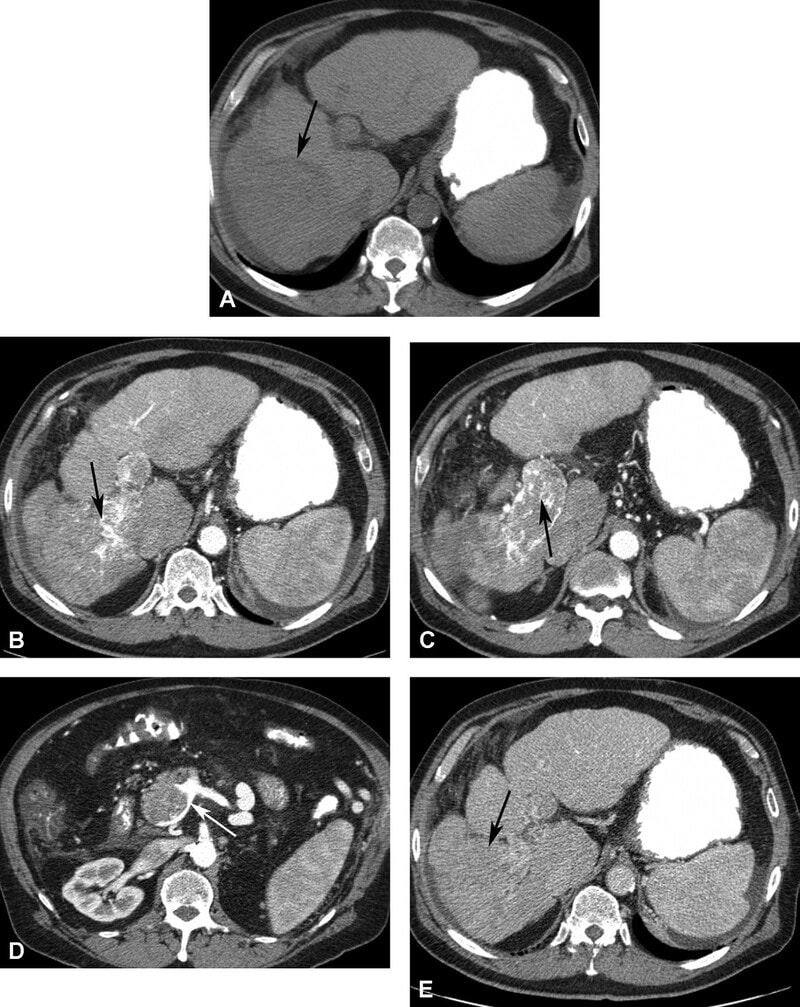

Trên CT không cản quang, HCC thường giảm đậm độ so với gan. HCC bắt quang thì động mạch và trở nên giảm đậm độ ở thì tĩnh mạch cửa (Hình 10). Viền bắt quang mỏng có thế có ở thì tĩnh mạch và thì muộn do giả bao. Thực hiện thì động mạch trễ (34 giây) đã được báo cáo cho thấy các nốt HCC hơn thì động mạch sớm (20 giây). Các hình thì động mạch sớm có khả năng chụp mạch CT 3D chất ợng tốt hơn để lập bản đồ mạch máu trước phẫu thuật. Thêm hình ảnh CT thì muộn (180 giây) đã được báo cáo để cải thiện độ nhạy và độ đặc hiệu trong phát hiện HCC so với CT hai pha.

Nói chung, HCC tăng tín hiệu trên T2W và giảm tín hiệu trên T1W. Hình MRI sau tiêm thuốc thấy bắt thuốc thì động mạch rõ rệt, không đều, thải thuốc nhanh ở thì tĩnh mạch và thì muộn (Hình 11). Phát sinh bắt thuốc viền ngoại vi do giả bao. Nốt loạn sản độ cao có thể bắt thuốc. Tuy nhiên, nốt loạn sản không có bao giả. HCC lan tỏa có tín hiệu không đồng nhất trên T1W và T2w, với bắt quang không đều, có các vùng thải thuốc và các vùng khác có thể còn đọng thuốc. Huyết khối do u ở tĩnh mạch cửa cho thấy bắt quang ở thì động mạch điển hình (Hình 10 và 11). Dấu hiệu này giúp phân biệt huyết khối do u với huyết khối lành tính, không bắt quang ở thì động m ạch. Bao u có thể thường gặp ở người châu Á, là các viền echo trống trên siêu âm và bắt thuốc viền ngoại vi ở thì trễ trên CT và MRI.

Hình 10. Bệnh nhân nam 62 tuổi xơ gan và carcinoma tế bào gan thâm nhiễm lan tỏa. CT không cản quang (A) thấy bờ ngoài gan dạng nốt kèm khối giảm đậm độ (mũi tên) ở thùy gan phải. CT thì độn g mạch (B) thấy khối bắt quang không đồng nhất (mũi tên). Huyết khối do u bắt quang không đồng nhất (mũi tên ở C) làm phình lớn tĩnh mạch cửa và lan đến chỗ hợp lưu tĩnh mạch mạc treo tràng trên (mũi tên ở D). U đồng đậm độ (mũi tên) với gan do thải thuốc ở thì tĩnh mạch cửa (E).

Hình 11. Bệnh nhân nam 62 tuổi xơ gan và carcinoma tế bào gan thâm nhiễm lan tỏa (cùng bệnh nhân ở hình 10). Khối giảm tín hiệu (mũi tên) trên hình T1W 3D GRE (A) và tăng tín hiệu (mũi tên) trên hình T2W SSFSE (B). Khối bắt thuốc không đồng nhất (mũi tên) ở thì động mạch với bờ lan tỏa (C). Huyết khối do u bắt thuốc không đồng nhất (D, mũi tê n) phình lớn tĩnh mạch cửa và lan vào hợp lưu tĩnh mạch mạc treo tràng trên (E, m ũi tên). Thì muộn (F) thấy u thải thuốc kèm bắt thuốc vách bên trong (mũi tên) và giả bao.